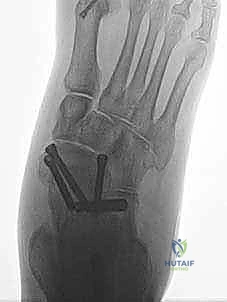

عندما يكون القرار الطبي هو التدخل الجراحي، فإن المرضى بين يدي الأستاذ الدكتور محمد هطيف يحظون بأعلى مستويات الرعاية الطبية المتاحة في اليمن. تُجرى هذه العملية المعقدة باستخدام تقنيات الجراحة المجهرية (Microsurgery) لضمان الدقة المتناهية، وغالبًا ما تُدمج مع استخدام مناظير المفاصل بدقة 4K لمعالجة أي إصابات غضروفية داخلية دون الحاجة لفتح المفصل بالكامل.

* الإصلاح المباشر (Direct Repair): إذا كانت أنسجة الرباط الممزقة ذات جودة جيدة (عادة في الإصابات الحديثة)، يقوم الدكتور هطيف بخياطتها مباشرة. يستخدم خطاطيف تثبيت عظمية (Suture Anchors) صغيرة جداً ومصنوعة من مواد متوافقة حيوياً (تذوب مع الوقت أو من التيتانيوم) لغرس الخيوط القوية في عظمة الكعب الإنسي، ثم يتم سحب الرباط الممزق وتثبيته بقوة في مكانه التشريحي الأصلي.

- إعادة البناء (Reconstruction): في الحالات المزمنة حيث يكون الرباط الأصلي قد تليف، تآكل، أو أصبح غير كافٍ للاستخدام، يلجأ الدكتور هطيف إلى تقنية "إعادة البناء". تتضمن هذه التقنية المتقدمة استخدام رقعة وترية (Graft)، إما من جسم المريض نفسه (Autograft - مثل أوتار الركبة أو وتر من القدم) أو رقعة صناعية متطورة. يتم حفر أنفاق ع